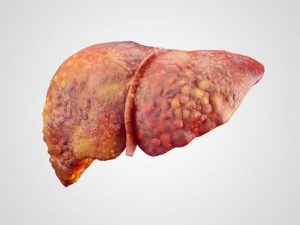

يتعرض الكثير من الأفراد إلى فترات لا يعمل فيها كبدهم بشكل صحيح، وهو ما قد يعتبر مؤشر على مشكلة صحية في الكبد مثل ارتفاع انزيمات الكبد حيث أن الكبد يكون مصاب بالتهاب أو مصاب بما يسمى تلف الخلايا في الكبد، وتتسرب تلك الخلايا بصورة أعلى من الطبيعي إلى مجرى الدم، وتحت شعار تجربتي مع ارتفاع انزيمات الكبد، خاص البعض تجارب مع تلك المشكلة الصحية.

- كما أن هناك العديد من الأمراض المرتبطة بالكبد تؤدي إلى الإصابة ارتفاع انزيمات الكبد ومنها التهاب الكبد أ، بالإضافة إلى التهاب الكبد ب، وأيضًا التهاب الكبد ج، وهناك أيضًا ما يسمى باسم مرض الكبد الدهني غير الكحولي، وما يسمى أيضًا بالتهاب الكبد المناعي.